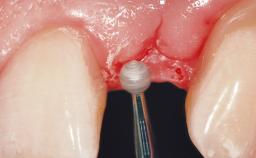

A 30-year-old female patient was referred to the office for the treatment of tooth 11. Her chief concern at the initial visit was to inquire, “Why is my tooth pink?” Upon clinical examination, it was determined that tooth 11 had a previous history of trauma and that the clinical crown had become noticeably pink in color as a result of internal resorption. This diagnosis was confirmed radiographically, indicating a large radiolucency involving the central and distal portions of the clinical crown. It was determined that restoration of this tooth was not possible, and that extraction was indicated. The presence of a mid-line diastema, which the patient wanted to reproduce, directed the treatment plan for tooth replacement utilizing a dental implant.

Placement Protocol Immediate implant placement

Tooth Site Maxillary incisor or canine